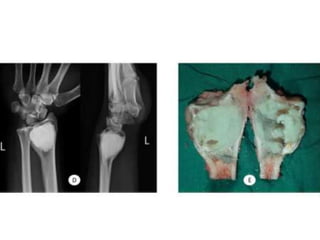

CASE REPORT

JULY 2009

SEPT 2009

1 year later

AUG 2010

JAN 2013

• MAY 2013

• DENOSUMAB started

• 360 mg subcutaneous dose

• Followed by 120 mg every month

OCT 2013

• Pain around knee joint diminished

• Further resection ??

• Patient refused

• Clinical improvement persisted until jan 14

• Presented with Rapidly growing painful

palpable mass

• Open biopsy : high grade sarcoma

• A/K amputation